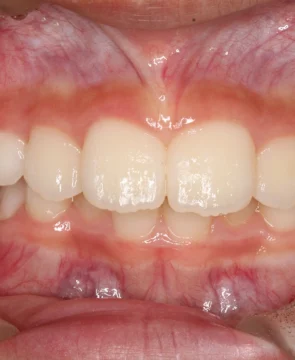

2026/04/14全体的な歯並びのがたつきが気になる10歳女児の矯正症例紹介 今回ご紹介する患者様は、全体的な歯並びのがたつきを気にされており、矯正検査後叢生Ⅰ級と診断いたしました。 治療前後の比較 矯正術前:正面 矯正術後:正面 矯正術前:右側 矯正術後:右側 矯正術前:左側 矯正術後:左側 矯正術前:上顎 矯正術後:上顎 矯正術前:下顎 矯正術後:下顎 矯正術前:前歯部あおり 矯正術後:前歯部あおり 矯正術前:オーバージェット 矯正術後:オーバージェット 主訴 全体的な歯並びのがたつきが気になる 治療期間 ・マウスピース矯正:10カ月 治療費用 …